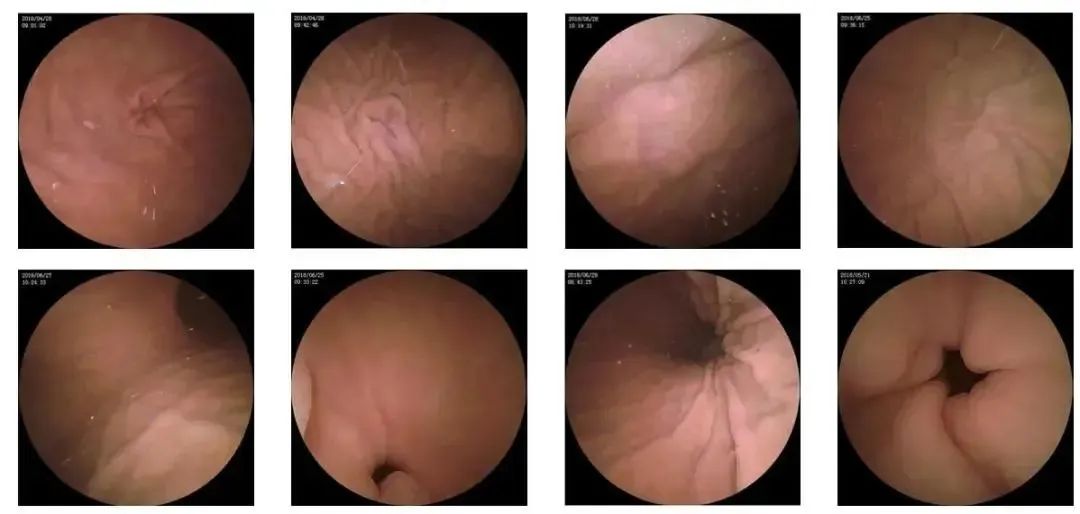

10—15分钟即可完成贲门、胃底、胃体、胃角、胃窦、幽门等解剖部位观察,让胃部检查更高效。更为重要的是,检查全程无痛、无创、无麻醉,避免了传统插管胃镜带来的生理痛苦。

胶囊机器人的专利三镜片镜头,可深入观察0.04毫米微小单位,每秒可拍高达4张高清医学照片。

医生通过智能阅片系统,可自动对海量图像识别过滤,智能筛选,能有效提升医生检查及阅片效率。

任何细微的胃部病变,如胃溃疡、胃出血、息肉等都无所遁形,尽在大圣磁控胶囊式内窥镜系统的掌握之中。

定期做检查的必要性

检查肠道内病变组织、做无痛活检、息肉、早期肠胃肿瘤等较好的方法,可对肛肠及胃肠内部深层病灶部位进行图像采集、实时诊断,医患双方在检查过程中可同时清晰的观察到放大数十倍的病灶部位,避免误诊、误治,从而为临床治疗提供可靠依据。